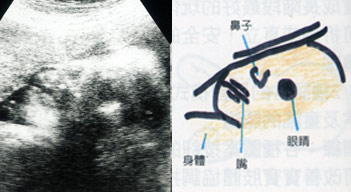

怀孕28周

怀孕28周

这张超音波照的胎儿,鼻子看起来还蛮高的唷!